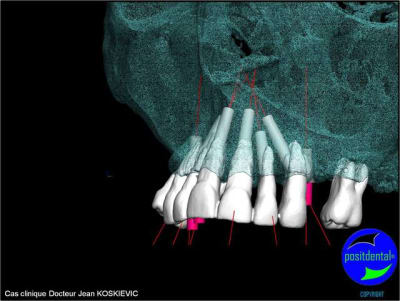

rendu 3D maxillaire sup, pano et photo

3D maxillaire inférieur et photo

et la projet 10 implants maxillaire sup